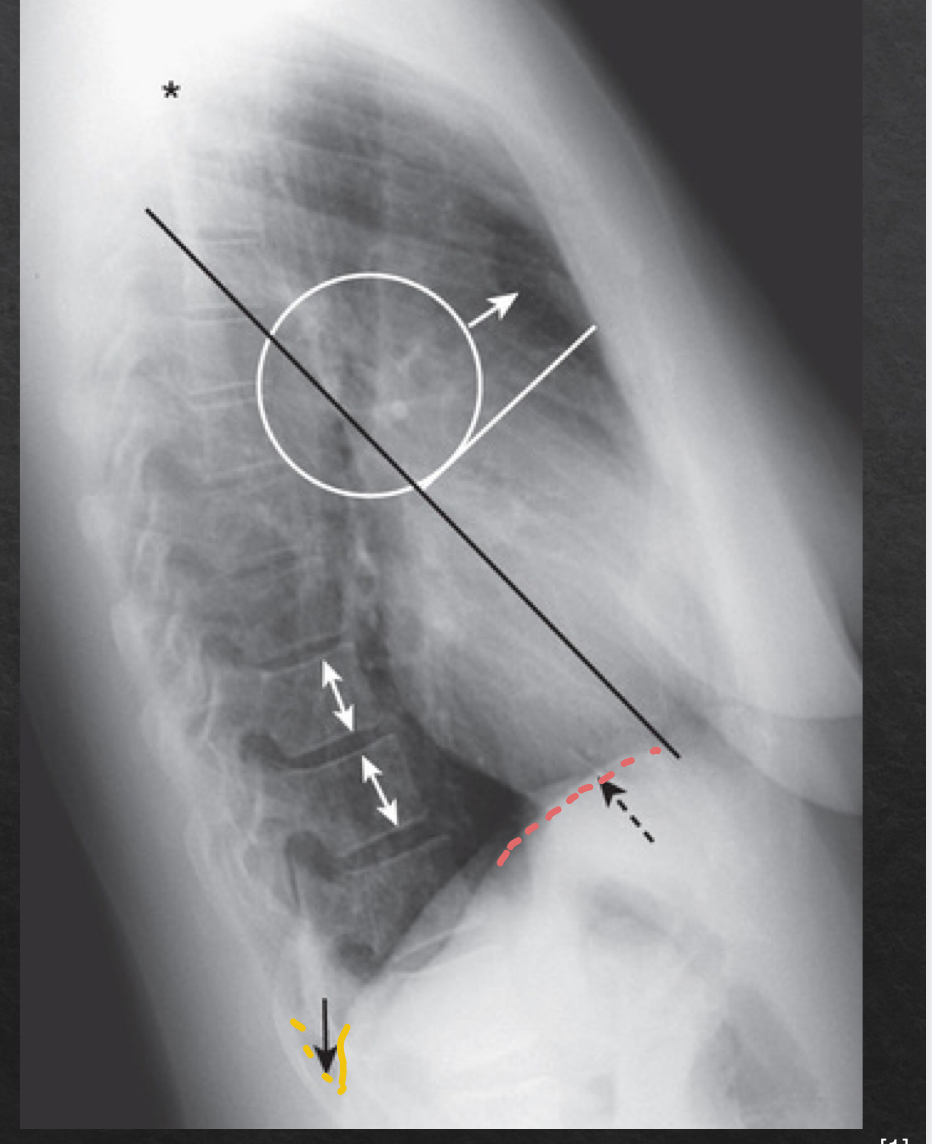

yellow: retrosternal spcae-clear

green: hilar region- no mass

red: fissures- VISIBLE

blue: thoracic spine- good

orange: diaphram and post costo sulci- slightly elevated